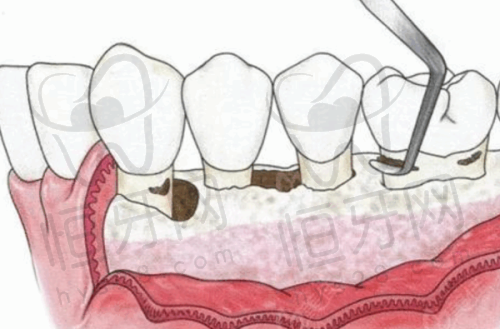

4. 口腔综合治疗项目:涵盖了补牙、拔牙、根管治疗、牙周治疗等常见的口腔疾病治疗。医院的医生具有丰富的临床经验,能够为患者提供专精、有效的治疗。